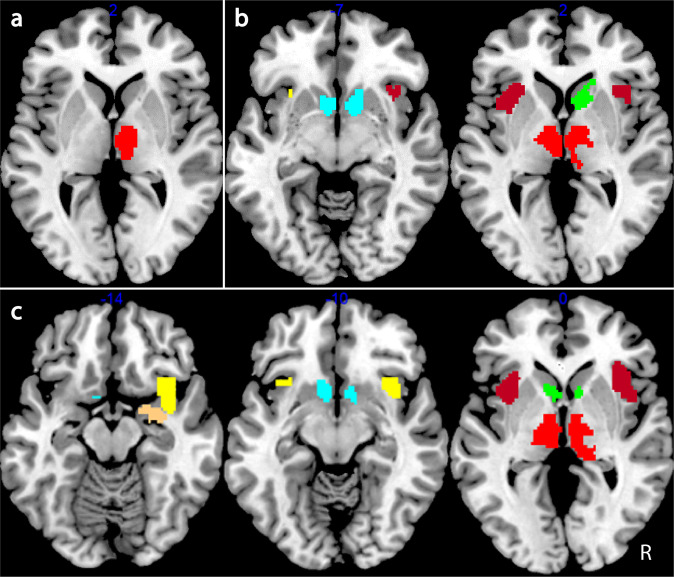

Table 2 and Fig. 2 present the results of the validation analysis. One-sample t-tests across all subjects confirmed that reward-related regions, assessed by region of interest (ROI) analysis, were more highly activated in both the valence and magnitude models, for the valence contrast with right thalamus being more highly activated for incentive conditions compared to neutral during the valence cue period. Additional regions were significantly more highly activated for incentive compared to neutral conditions during the presentation of the magnitude cue including the left: thalamus and ventral anterior insula, right: caudate, as well as bilateral: dorsal anterior insula and nucleus accumbens (NAcc). The magnitude contrast revealed high magnitude cues compared to low magnitude plus neutral ones further activated the right: ventral anterior insula and amygdala and left: caudate. There were no differences in activation for the reward versus punishment contrast in any pre-defined ROI.

Imaging main analysis

Based on the results of the validation analysis, the main analysis was carried out on the contrasts for the magnitude model. Between-subjects results of the main analysis including the effects of cannabis, schizophrenia and their interaction are presented in Table 3. There were no between group differences, nor interaction for the valence contrast. The main effect of cannabis use and an interaction of cannabis use and schizophrenia was observed for the reward versus punishment contrast. Extraction of beta values showed an increased activation in the right: putamen, ventral anterior insula and dorsal anterior insula for reward versus punishment for cannabis users (HC + C and SZ + C) compared to non-users (HC−C and SZ−C). Also activation in the right thalamus was larger for reward versus punishment for the HC + C and SZ−C groups versus HC−C and SZ + C groups (Fig. 3a). For the magnitude contrast, there was no main effect of cannabis use nor schizophrenia while the interaction of these two factors appeared for left: ventral anterior insula, dorsal anterior insula and bilateral posterior insula. Following beta value extraction it was shown that HC + C exhibited increased activation in each of the above-mentioned regions compared to HC−C, while the opposite pattern was observed for patients, namely SZ + C displayed activation decreases in all of these regions compared to SZ−C (Fig. 3b).

A much more interesting picture emerged when considering the interaction of cannabis and schizophrenia on reward-related activation. The increase in activation for high magnitude cues compared to low and neutral ones in left: ventral anterior insula, dorsal anterior insula and bilateral posterior insula was larger in HC + C and SZ−C compared to HC−C and SZ + C replicating the results that were observed behaviourally for reward-related sensitivity. The increase in activation related to reward anticipation for control chronic cannabis users compared to non-users confirms our first hypothesis and is in accordance with the previous research16. However in contrast to our second and third hypotheses we observed increased activation for high magnitude cues in non-user patients and a decrease in activation for chronic user schizophrenia patients. These opposing effects compensated for each other so that in the total group of patients there was no difference in reward-related sensitivity when compared to the total group of controls that is in accordance with previous studies of schizophrenia patients receiving atypical antipsychotics24,25,27. Again it is important to note here that all of these previous studies have not included chronic cannabis use as a factor in the analysis of reward-related sensitivity in schizophrenia.

The majority of research on the involvement of insula on reward anticipation has focused on the anterior sub-region31,32, which has been found to be involved in the assessment of risk for upcoming events34. Previous studies have shown functional activation differences of chronic cannabis users35 and schizophrenia patients36 compared to controls in the anterior insula but the combined effects of both groups on activation of this area were not investigated. In the current study we observed an interaction effect of cannabis use and schizophrenia on reward anticipation-related activation on both anterior and posterior insula. Previous research has suggested that increased activity of the posterior insula during reward anticipation may indicate increased somatosensory arousal37. The present study showed a specific increase in activation of the left anterior and bilateral posterior insula in relation to high magnitude cues in HC + C and SZ−C compared to HC−C and SZ + C suggesting a sensitization of these reward anticipation-related areas by chronic cannabis use and schizophrenia that diminished when both factors were present.

In response to valence anticipation, thalamic activation has been found to signify an “alerting” response, converging with insular information to guide action selection in NAcc38. In this study we observed an increase in right thalamic activation for reward versus punishment cues in HC + C and SZ−C compared to HC−C and SZ + C. This interaction effect once again suggests a reward-specific sensitization produced by chronic cannabis use and schizophrenia that was reversed when both factors were present.